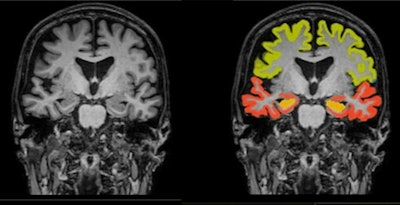

Dementia MRI with segmentation. Image and caption courtesy of Icometrix.The company noted that it's collaborating with Kathleen Poston, MD, a professor of neurology and neurological sciences at Stanford Medicine. She heads a research project evaluating volumetric patterns of brain MRI scans and correlating these to corresponding clinical scores for motor and cognitive function, according to Icometrix.

Poston presented initial findings at the recent 2023 Alzheimer's and Parkinson's Disease Conference, showing that regional brain volumetry assessment can serve as an important biomarker in prediction and differentiation of PD patients at risk for motor and/or cognitive disability progression.